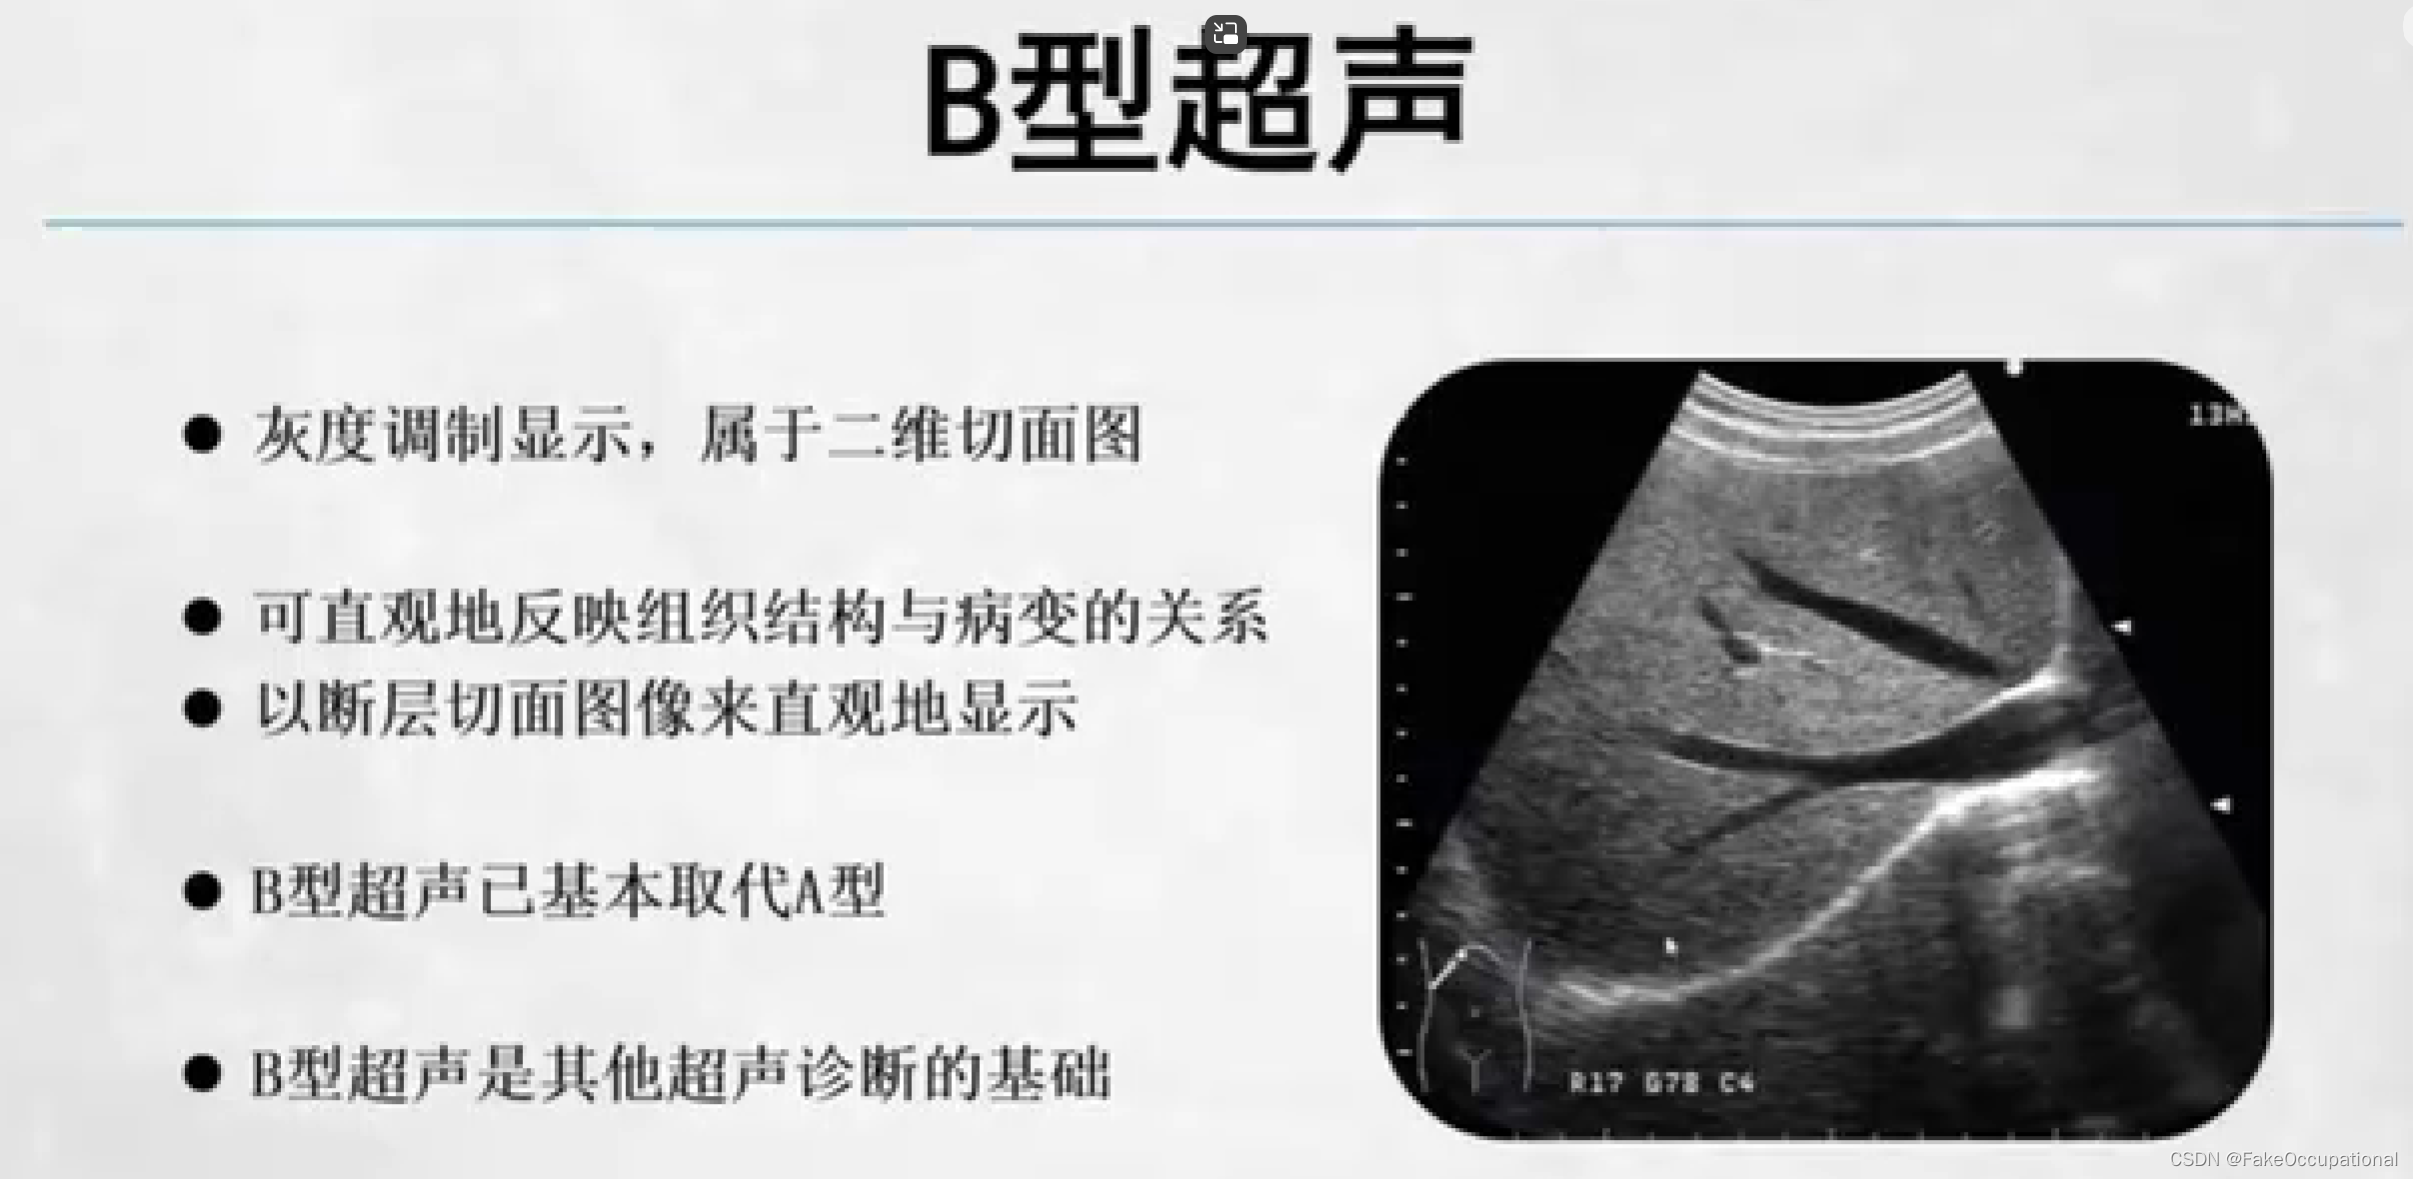

超声成像方法包括A型,B型,M型,D型(频谱多普勒,多普勒血流成像)。